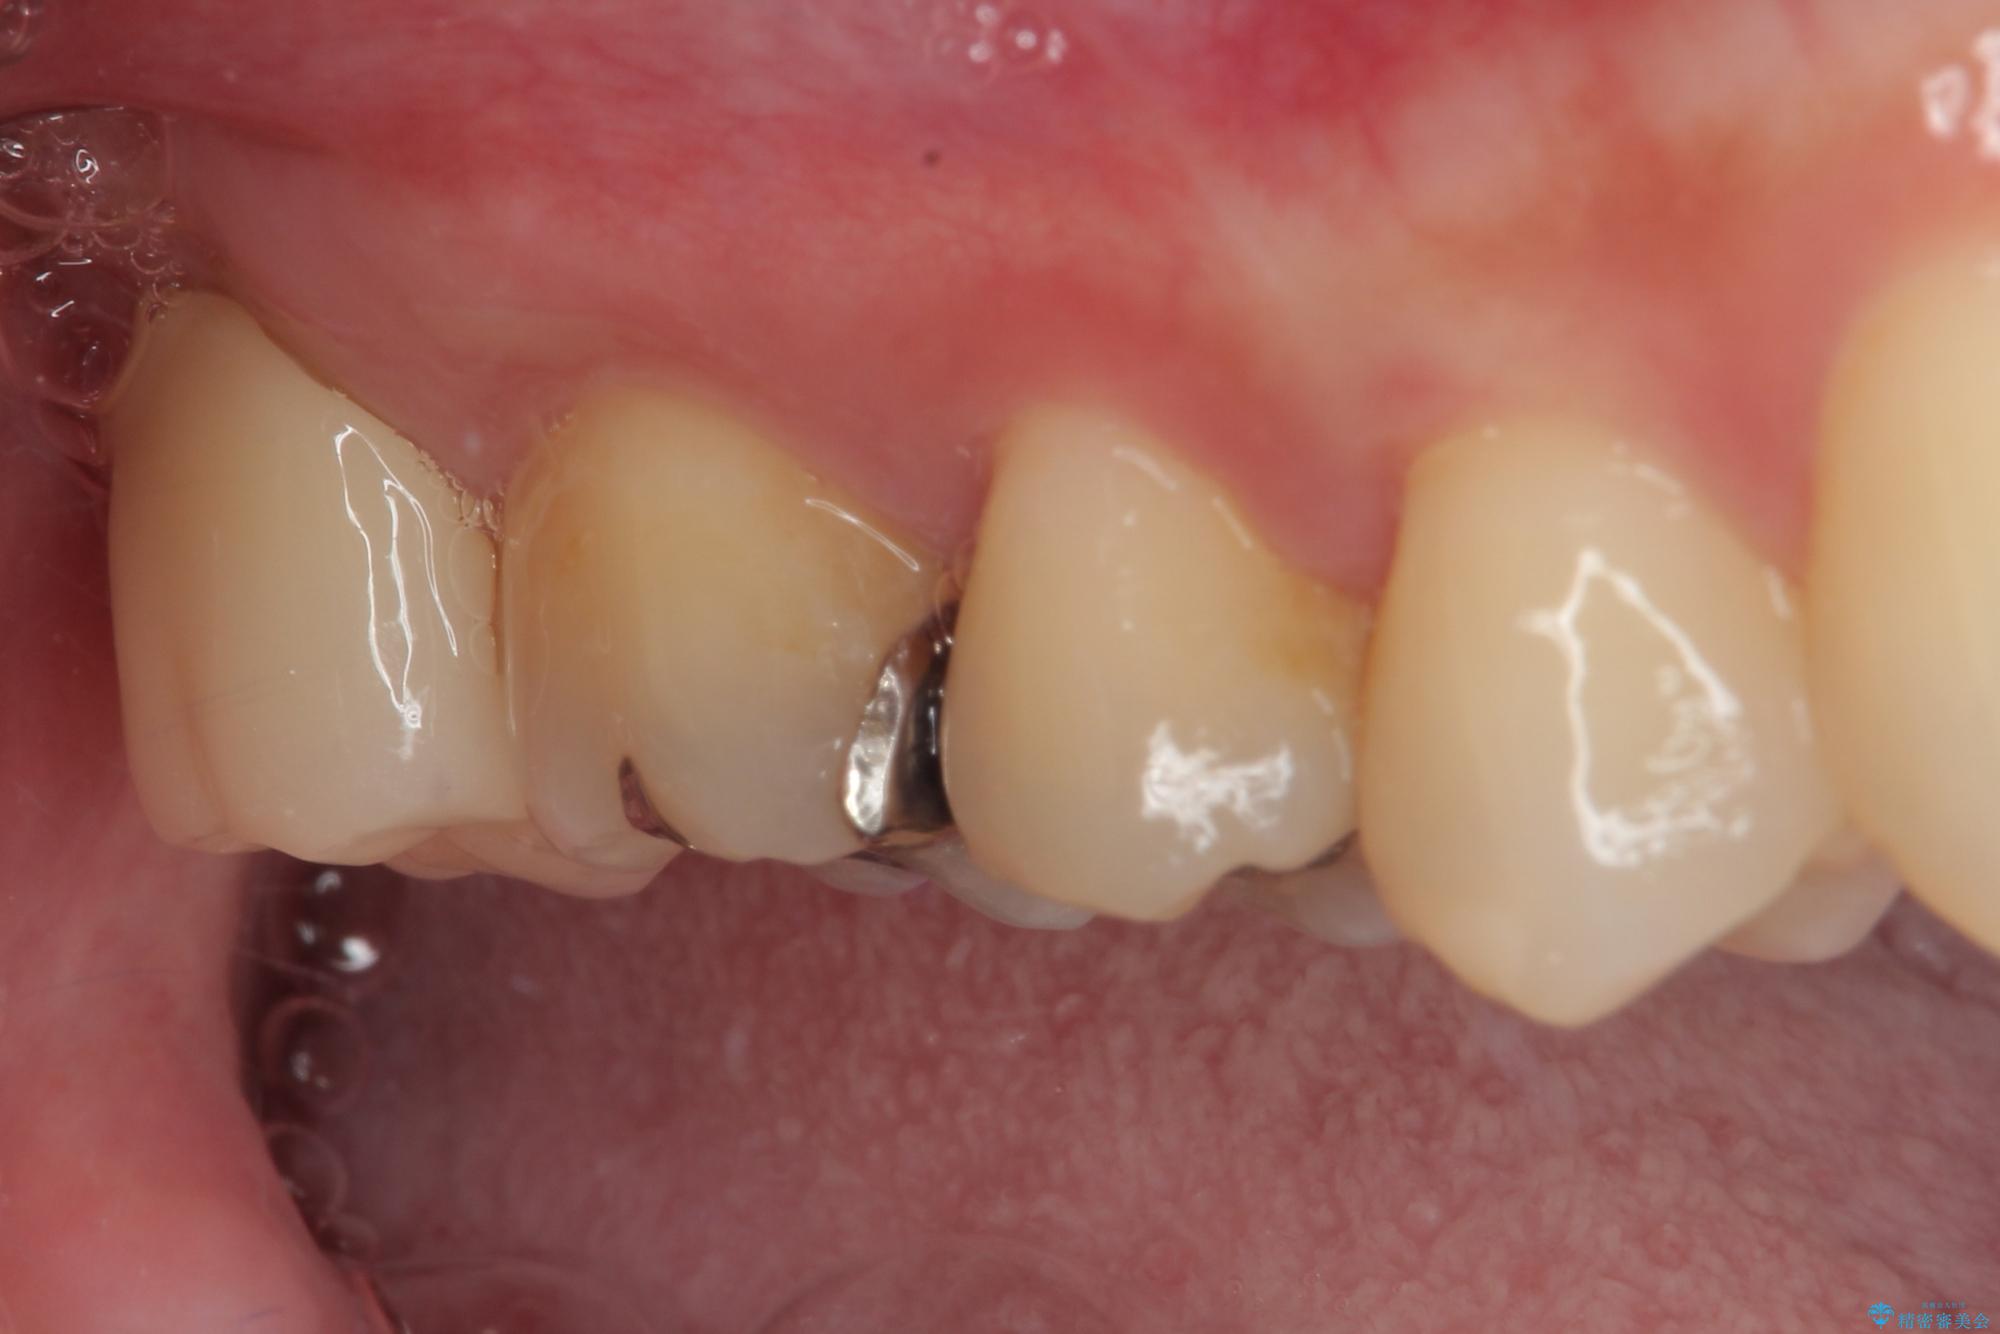

- 元々むし歯があったものの、処置が困難とのことでしたが、矯正治療を終えたので処置をしたいとのことで来院された患者様です。

左右ともに最後臼歯が頬側に顕著に突出しており、むし歯になってしまったことが想像されました。

矯正治療により処置が可能な位置に歯が移動したため、オールセラミッククラウンにて補綴治療を行うこととしました。

歯列が移動したとはいえ、左右ともに後方傾斜しており、むし歯の除去、形成(形を整える)、型取りの全てが非常に困難な処置となりました。